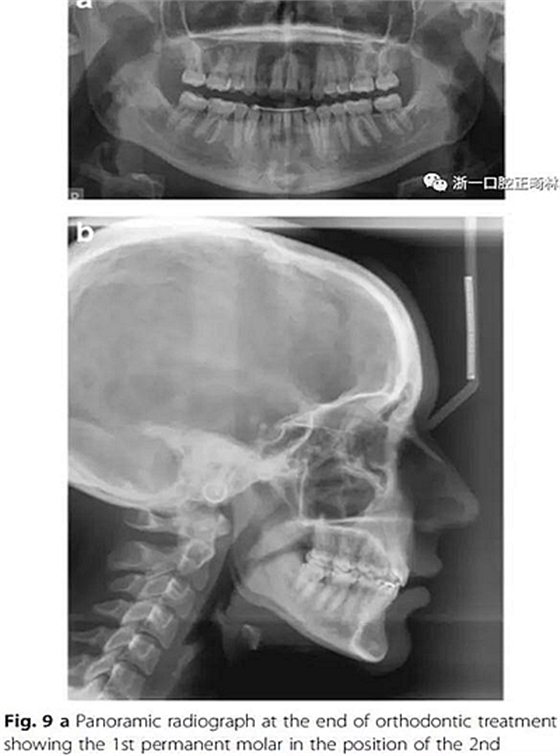

治療結(jié)果

雙側(cè)I類尖牙和磨牙關(guān)系;完全的間隙關(guān)閉(用牙線確定);覆合覆蓋糾正;仍有輕度的中線偏離。頭測(cè)分析顯示,下切牙未發(fā)生舌側(cè)移動(dòng)。